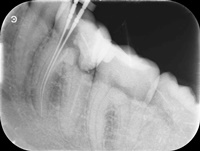

Przed trzema laty ząb 16 (prawa górna szóstka) był przeleczony endodontycznie i wykonano most. W ciągu 18 miesięcy od osadzenia mostu pacjentce kilka razy formował sie ropień dziąsła, osiem razy podawano antybiotyki. Gdy to nie pomagało, wykonano resekcję policzkowego korzenia zęba 16. Nie pomogło. W dalszym ciągu dochodziło do stanów zapalnych i antybiotykoterapii. W tym stanie pacjentka zgłosiła się, do naszego gabinetu. Zdjęto most, przeprowadzono ponowne leczenie kanałowe. Po sześciu miesiącach wykonano nowy most. Upłynęło półtora roku. Nie dochodzi do nawrotów stanu zapalnego, ani obrzęków. Ten przypadek pokazuje, dlaczego tak ważne jest poprawnie wykonane leczenie kanałowe, według nowoczesnego protokołu leczenia.